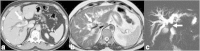

Malignancies of the biliary tract include cholangiocarcinoma, gallbladder cancers and carcinoma of the ampulla of Vater. Biliary tract adenocarcinomas are the second most common primary hepatobiliary cancer. Due to their slow growing nature, non-specific and late symptomatology, these malignancies are often diagnosed in advanced stages with poor prognosis. Apart from incidental discovery of gall bladder carcinoma upon cholecystectomy, early stage biliary tract cancers are now detected with computed tomography (CT) and magnetic resonance imaging (MRI) with magnetic resonance cholangiopancreatography (MRCP). Accurate characterization and staging of these indolent cancers will determine outcome as majority of the patients' are inoperable at the time of presentation. Ultrasound is useful for initial evaluation of the biliary tract and gallbladder masses and in determining the next suitable modality for further evaluation. Multimodality imaging plays an integral role in the management of the biliary tract malignancies. The imaging techniques most useful are MRI with MRCP, endoscopic retrograde cholangiopancreatography (ERCP), endoscopic ultrasound (EUS) and positron emission tomography (PET). In this review we will discuss epidemiology and the role of imaging in detection, characterization and management of the biliary tract malignancies under the three broad categories of cholangiocarcinomas (intra- and extrahepatic), gallbladder cancers and ampullary carcinomas.